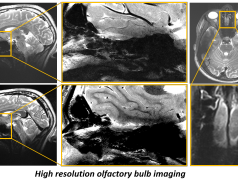

High resolution anatomical imaging